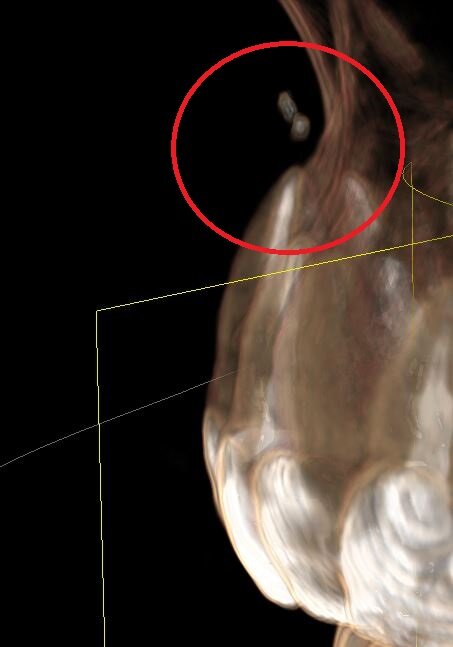

Как стоматологи могут сделать проблему в жизни, даже и не знала что может быть такое. Лечила корни верхнего клыка - обычный пульпит, удалили нерв и запломбировали каналы зубов гуттаперчей. После лечению дня 4 не отходила заморозка. Потом все как-то прошло, через некоторое время у носа образовалась опухоль. Сделали томограмму, оказывается силер или гуттаперча - пломба, чем врач набивает каналы зубов вышел за верхушку корня, и далеко, на томограмме видно что масса вышла за пределы черепа, и застряла в мягких тканях видимо. И эта масса пломбировочного материала - силер вызывает аллергию и опухоль. Верхушка корня - основание корня, его начало. Зуб не болит, не беспокоит, при нажатии ничего не болит, только лицо опухшее и несимметричное. И мой нос и так с перекошенными носовыми перегородками внутри, после того как по нему не хило долбанули, стал еще более неправильной формы (как бы это написать).

Как стоматологи могут сделать проблему в жизни, даже и не знала что может быть такое. Лечила корни верхнего клыка - обычный пульпит, удалили нерв и запломбировали каналы зубов гуттаперчей. После лечению дня 4 не отходила заморозка. Потом все как-то прошло, через некоторое время у носа образовалась опухоль. Сделали томограмму, оказывается силер или гуттаперча - пломба, чем врач набивает каналы зубов вышел за верхушку корня, и далеко, на томограмме видно что масса вышла за пределы черепа, и застряла в мягких тканях видимо. И эта масса пломбировочного материала - силер вызывает аллергию и опухоль.

Силер вышедший за верхушку корня может со временем рассасываться медленно, годами.

Кроме того силлер вышедший по ошибке врача за пределы корня может вызвать парестезию, то есть потерю чувствительности, об этом статья

У меня тоже долго не возвращалась чувствительность, я думала это анестезия, кроме того, у меня до сих пор это место слабо чувствует.